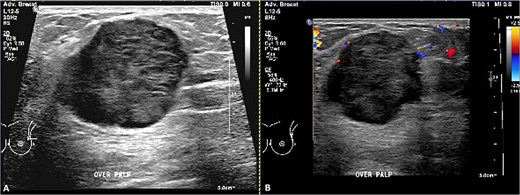

Breast ultrasound showed a fatty background with a 3.6 × 3.3 × 3.0 cm round, heterogeneous hypoechoic mass at 2 o’clock with indistinct margins and internal vascularity, and a single prominent but benign appearing left axillary node (Fig. 1A and B). Mammography revealed almost entirely fatty parenchyma (ACR A) with a hyperdense left upper outer quadrant mass, without calcifications or architectural distortion (BI-RADS 4C on the left, 1 on the right) (Fig. 2A and B).

Ultrasound of the left breast. (A) Grayscale and (B) color Doppler images demonstrate a vertically oriented, microlobulated, heterogeneously hypoechoic mass at the 3 o’clock position in the distal left breast, showing peripheral rim vascularity.